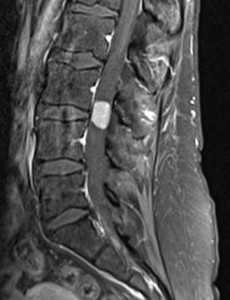

Изменения сигнала по типу MCh2 характеризуются гиперинтенсивным сигналом на T1- и Т2-ВИ и обусловлены жировой дегенерацией костного мозга (рис. 2). Гистопатологический анализ демонстрирует разрушение КПП и образование грануляционной ткани без гиперваскуляризации, замену костного мозга жировой тканью [2, 12].

Рис. 2. Изменения на МРТ по типу MCh2. 1 — гиперинтенсивный сигнал на T1-ВИ; 2 — гиперинтенсивный сигнал на Т2-ВИ; 3 — гипоинтенсивный сигнал в режиме подавления сигнала от жира (STIR).